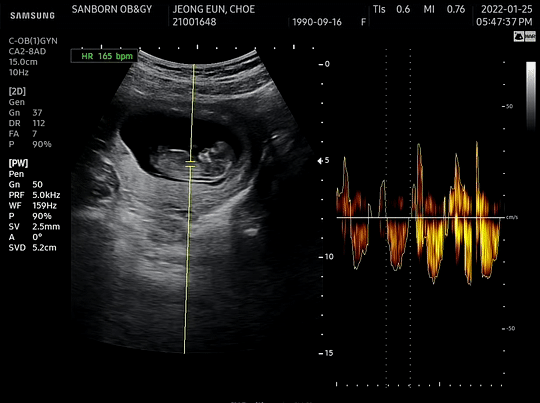

[10주차 호띵이 초음파 (10주차)]

위의 초음파영상을 보면서 호띵이가 8주차 대비 2배나 큰것을 알 수 있었다.

- 7주차 : 1cm 미만

- 8주차 : 1.98cm

- 10주차 : 4.05 cm (8주차 대비 2배나 컸다)

호띵엄마 말로는 의사선생님께서 별 탈 없이 아주 잘자라고 있다고 해서 기다리다가 지쳤던 마음이 금새 풀렸다.

초음파 영상을 쭉 보면 처음에는 아주 얌전히 있던 호띵이가 심장박동수 체크를 하니 팔과 다리를 우렁차게 움직이는 모습을 보면서 호띵이가 심장박동 체크하는 것을 얼마나 힘들어하면 애가 저렇게 움직일까 싶다가도 호띵이 팔 다리 그리고 귀와 머리가 아주 잘 크고 있는 것을 보면서 내심 뿌듯했다. 엄마 뱃속 아주 작은 공간에서 꿋꿋히 잘 버티는 호띵이의 모습이 기특했기 때문이다.